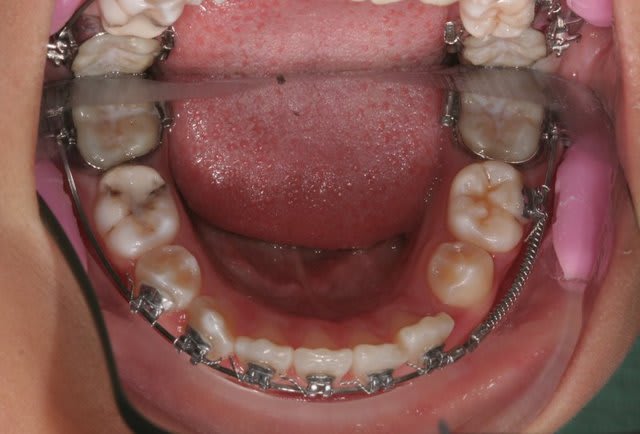

j'ai revu le jeune patient(7,5 ans) aujourd'hui.

En fait, il porte un multi bagues sur les 4inc associé à un quadhélix.

C’est la technique segmentée de Ricketts.

Technique utilisée en interception, elle a pour but de corriger très tôt les axes des incisives.

Et par le Q.H. de déroter les 6 (canines postérieures) pour déverrouiller la croissance, ainsi que de verser les dents lactéales qui vont entraîner les germes des dents permanentes et ainsi faire une expansion avec de l’os.

C’est une excellente technique d’interception, bien que pas toute jeune. C’est dommage que tu n’en ais pas vu plus souvent.

Les douleurs viennent souvent du Q.H. qui en travaillant peut appuyer sur le palais, ou des crochets extérieurs sur les bagues.